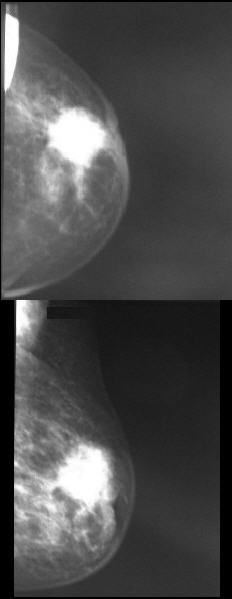

| Histologically proven breast cancer did not return a positive CAD result in either the craniocaudal or mediolateral oblique views. Image courtesy of Dr. Valentina Annibale. |

The researchers found that three of the 83 (4%) histologically proven breast cancers did not return a positive result in their CAD analysis in either the craniocaudal or mediolateral oblique views. In addition, they reported that in nine of the 83 patients, the CAD analysis showed the lesion in only one projection.

In the CAD false-negative group for both craniocaudal and mediolateral oblique projections, two of the three patients had a nodular lesion while the remaining patient presented with a parenchymal distortion. In the group with false-negative CAD in one of the two projections, four patients had a nodular lesion, four had nodular lesions with microcalcification, and one patient had both parenchymal distortion and microcalcification, according to the researchers.